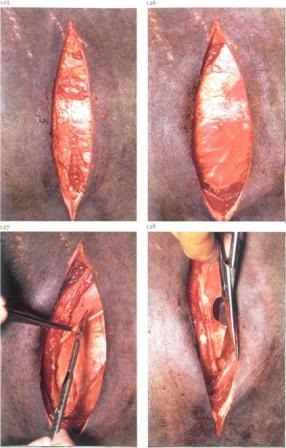

Incizia: este produs lungime adecvată verticală (a se vedea figura).

corn gravidă (stânga sau dreapta, oricum!) trebuie să fie localizat în partea dreaptă a abdomenului,

Uterul trebuie să fie rotit și penetrat mâna dreaptă sub uterului, este necesar să se înțeleagă vârful suprafeței dorsomedial a articulației (cot sau Hock) de vițel.

Următoarea parte a uterului este rotit cu 90 de grade și trăgând în partea de sus a uterului, care găzduiește piciorul de vițel în timp ce împinge în direcția opusă o altă parte a uterului. Seize mâna grasps metatarsiene sau os toc. Mâna stângă zvlekayut uterului și de vițel afară. În zona osului călcâi este tăiat. Secțiune prin peretele uterin de-a lungul marii curburi de aproximativ 5 cm (în cazul unei poziții din spate, capul este sprijinit pe partea dreaptă, uterul este exteriorizat la stânga chișiță și o fantă în curbura mai mare se face pe Metacarpiene). lanțuri sterile elimina încet rodul membrelor. după care uterul este închis. Utilizarea forceps fălci: a scăpa de fluide placentar. (Nu ar trebui să cadă în cavitatea abdominală) Carve margine placentară. Uterul a fost suturată.